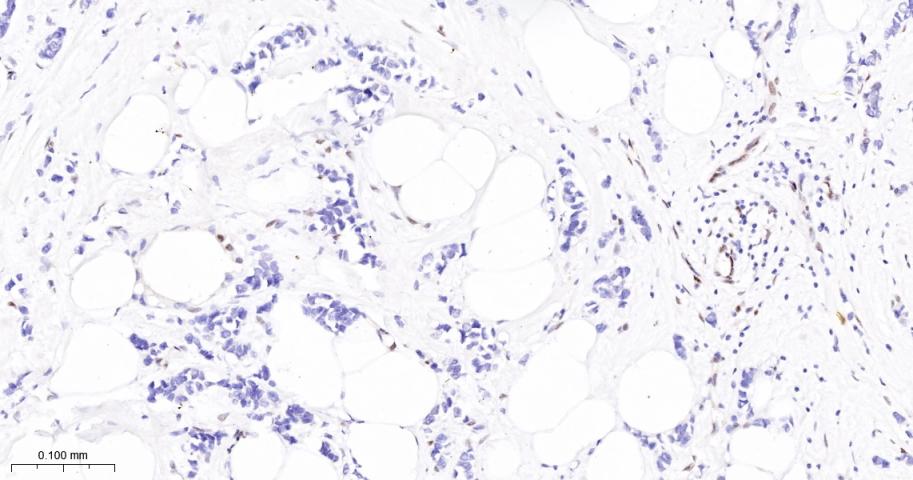

Paraformaldehyde-fixed, paraffin embedded Human Breast Cancer; Antigen retrieval by boiling in sodium citrate buffer (pH6.0) for 15 min; The section was incubated with JUNB Monoclonal Antibody, Unconjugated (bsm-60454R) at 1:200 overnight at 4°C, followed by conjugation to the bs-0295G-HRP and DAB (C-0010) staining.